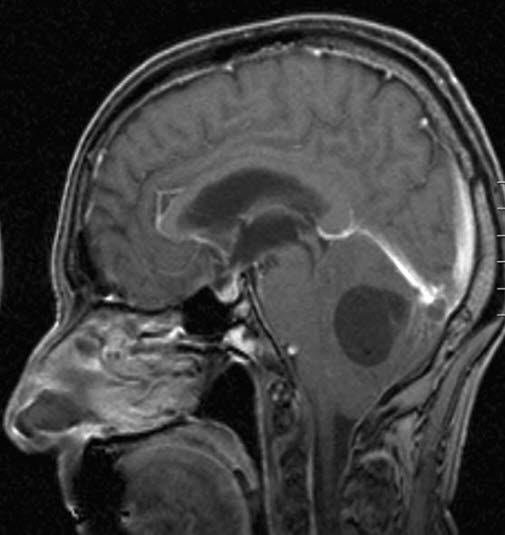

Hemangioblastom, sagittalt snitt

Gjengitt med tillatelse av Radiologisk avdeling, Universitetssykehuset Nord-Norge